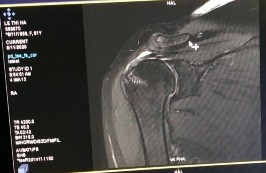

Bệnh nhânn nữ 60 tuổi, tiền sử khoẻ mạnh. Bệnh nhân xuất hiện đau vai phải cách đây đã lâu, đau nhiều về đêm và khi đưa tay lên cao. Bệnh nhân đã khám và điều trị tại bệnh viện tỉnh nhiều lần nhưng không đỡ. Bệnh nhân đến khám và nhập bệnh viện Đại học y Hà Nội ngày 15/01/2019. Khám thấy đau âm ỉ vùng vai, vai hạn chế giạng và đưa trước khoảng 60 độ, hạn chế xoay trong và hạn chế xoay ngoài. Khám các test phát hiện chèn ép khoang dưới MCV và tổn thương gânn chóp xoay thấy: Neer test (+); Speed test (+); Jobe test (+); Patte test (+); Drop arm test (-); Bear Hug test (-), trên phim MRI chụp trước mổ có hình ảnh rách nhỏ gân chóp xoay. Bệnh nhân được tiến hành phẫu thuật khâu gân chóp xoay ngày 16/01/2019 bằng 01 neo. Đánh giá điểm ASES trước mổ và sau mổ là 11,67 và 98,33 điểm UCLA sau mổ là 33, bệnh nhân rất hài lòng và cảm thấy tốt hơn rất nhiều so với lúc chưa mổ.

Hình phụ lục 1B: Hình ảnh rách nhỏ gân trên gai (Nguồn: BN nghiên cứu)